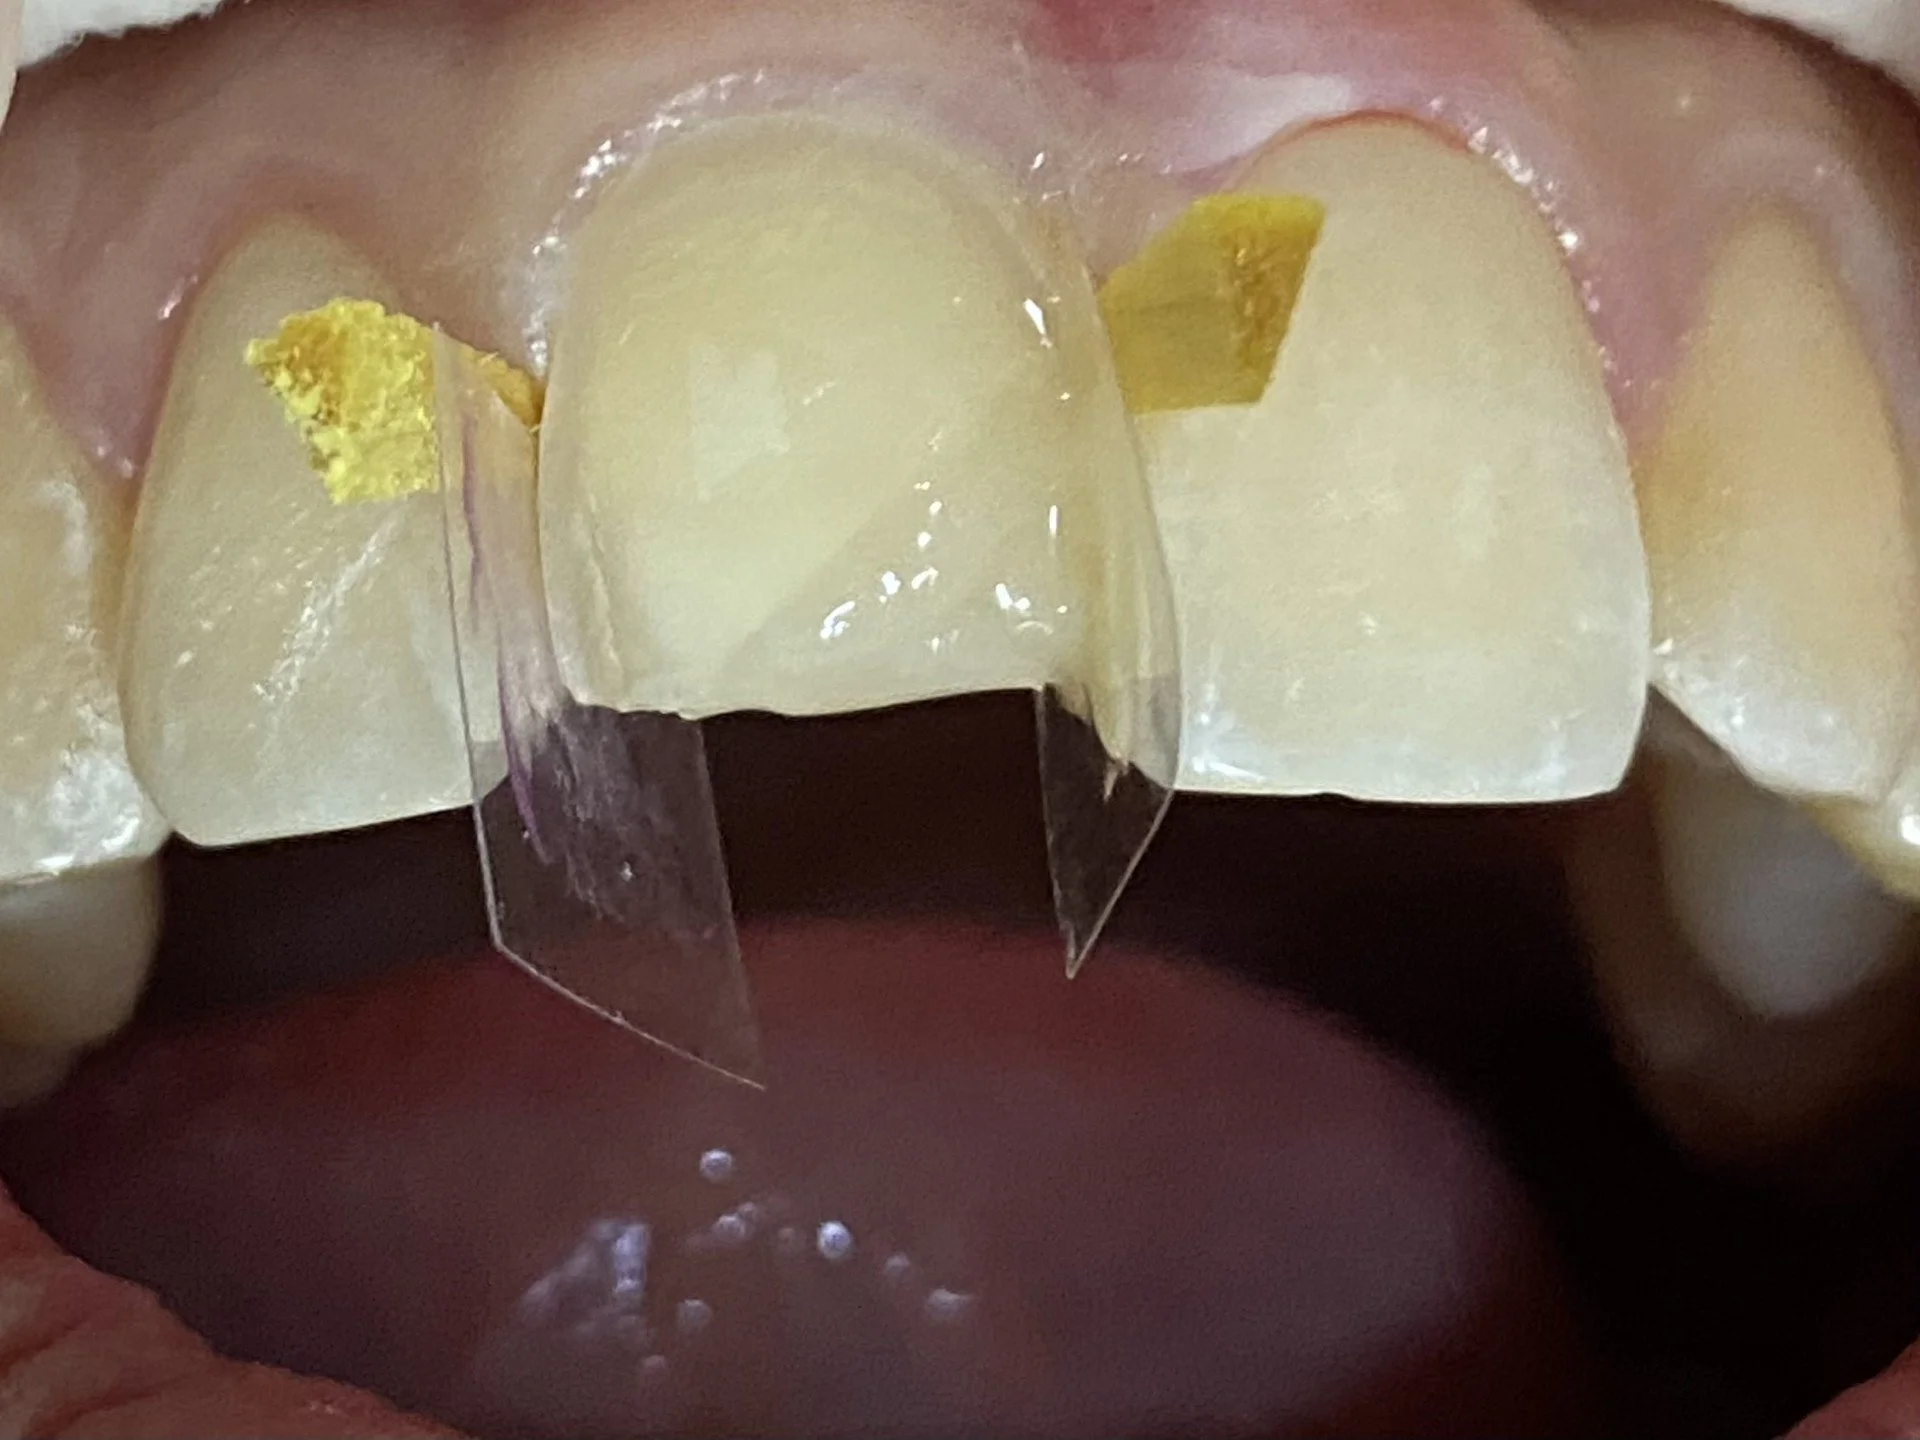

A comprehensive cavity preparation for an overlay was prepared by Dr. Michael Darveniza in Lismore. This entailed a full frontal veneer bevel (but 0.5 mm above the gum line) with an incisal step and a retentive slot at the base of the cavity with a moderate area veneer bevel on the back of the tooth. The yellow pieces of wood are called wedges and secure the clear plastic strips to prevent the filling material getting stuck below the gum.